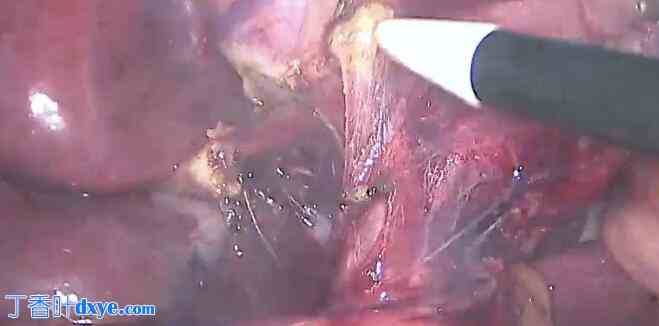

GB 膨胀

针刺减压后

GB 向右肩回缩

粘连松解

这是十二指肠

这是血管

从calot区剥离腹膜反折

沿胆囊壁进行侧方腹膜分离

另一个进入/离开GB的结构

沿胆囊壁进一步解剖,以明确该结构

这是位于胆囊右侧的高弓右肝动脉

右侧发出小胆囊动脉

注意,这条动脉位于Rouviere沟之上

沿胆囊壁进行内侧腹膜分离

为了确保在胆囊壁区域的安全,请沿胆囊壁进行解剖

这是胆囊管

这是左肝管,其位置异常高,高于rouviere沟水平

注意,这条肝管的位置也高于Rouviere沟

似乎是细小的血管分支

夹闭胆囊动脉